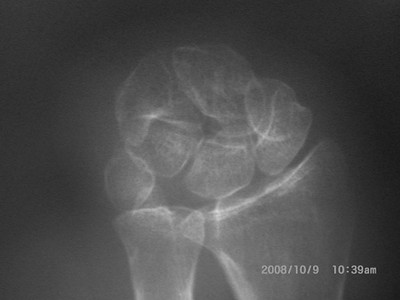

足踝伤病案例

足踝创伤

再造